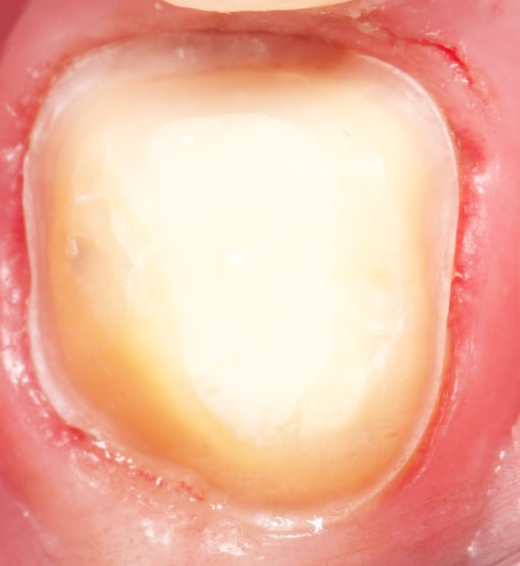

Аринин Дмитрий Юрьевич: портфолио (3)